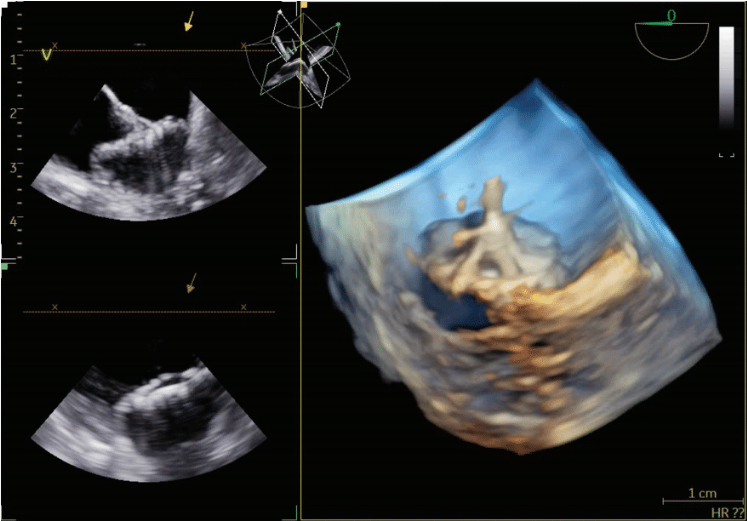

quickly adopted for most cases. The typical workflow for incorporating the 4D ICE catheter involves femoral venous access in the usual manner. To begin a case, the catheter is inserted into the right atrium (RA) and screened for pericardial effusion. Using the V-Plane feature, the LV pericardium can be visualized as well. The catheter is then deflected across the tricuspid valve and into the right ventricular outflow tract. V-Plane through the appendage, in addition to standard 2D imaging, can exclude LAA thrombus (Figure 1). The catheter is withdrawn back to the RA and imaging of the interatrial septum is obtained to help guide transseptal puncture in the usual manner. Once puncture is completed, the septum is flossed with the transseptal sheath. The sheath is then pulled back to the inferior vena cava (IVC). The ICE catheter is then withdrawn to the low RA with direct visualization of the wire as it crosses the septum. Under ultrasound and fluoroscopic guidance, the ICE catheter is pushed across the septum into the mid LA. The delivery sheath is then pushed across the puncture site into the LA. The ICE catheter can be positioned in different locations throughout the LA; however, placement along the mitral annulus frequently allows adequate visualization of the LAA (Figure 2). Multiplanar imaging of the LAA allows for device sizing and selection (Figure 3). Once a device size is selected, the implant is prepped and delivered using multiplanar and fluoroscopic imaging. During sheath manipulation and device delivery, the sonographer can make fine adjustments to the image to maintain adequate visualization so the operator can focus on device delivery. Once an implant is delivered, confirmation of position and occlusion can easily be performed by color flow Doppler and 2D/3D imaging (Figure 4). At the end of the procedure, a quick survey can exclude pericardial effusion.